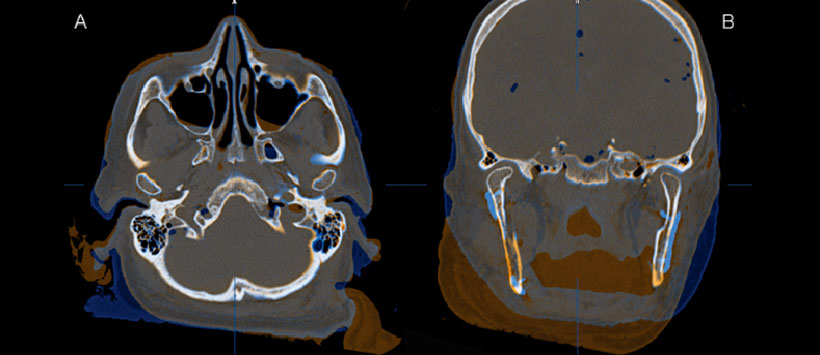

Se muestra el caso de una reconstrucción mandibular en un cráneo, se obtuvo un escaneo de tomografía computarizada multicorte (TEM) de un cráneo y peroné, La planificación se realizó utilizando el software de planificación ProPlan CMF (Materialise® / DePuy Synthes®). La sesión de planificación se realizó a través de una reunión en la web (GoToMeeting®, Citrix Online, Santa Bárbara, CA) entre ingenieros de Materialise® y DePuy Synthes® y los cirujanos. Durante toda la sesión de planificación, los ingenieros operaron el sistema informático y los cirujanos dieron instrucciones verbales sobre la base de los requisitos médicos. Usamos una placa de reconstrucción fresada fabricada con CAD / CAM específica del paciente junto con un colgajo de peroné de seis segmentos para el procedimiento de simulación en un intento de crear un caso que fuera más complejo y más desafiante que los casos estándar.

Primero, se establecieron los planos de resección de la mandíbula (Fig. 2). El tamaño del segmento mandibular que debe resecarse generalmente está determinado por la extensión de la patología a tratar. Los hallazgos clínicos y especialmente las tomografías computarizadas de diagnóstico (TC) juegan un papel clave en este contexto.